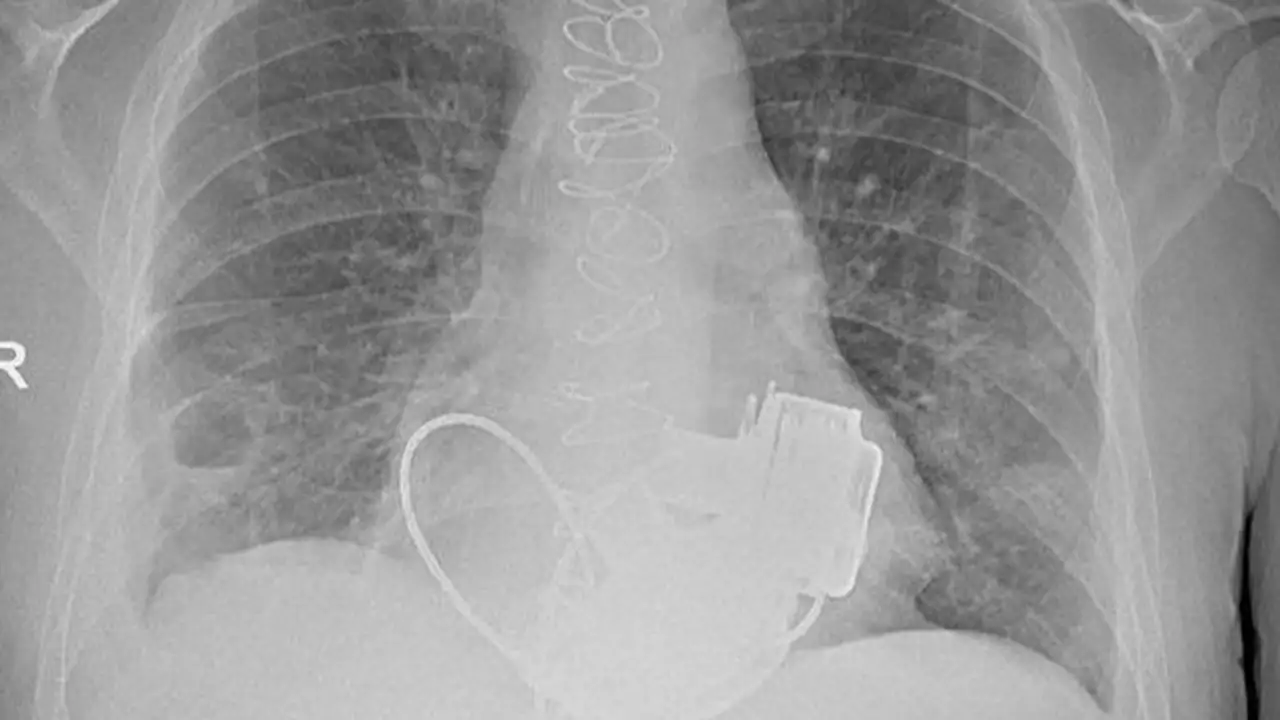

Пациент действительно уникальный — он живет без пульса, после того как в конце ноября 2025 года впервые в России ему были установлены два искусственных желудочка сердца — как левый, так и правый.

Мужчина попал в стационар с серьёзными проблемами сердца: кардиомиопатией и последней стадией сердечной недостаточности. Также у него наблюдались осложнения, включая тромбоэмболию лёгочной артерии и инфаркт-пневмонию, из-за чего трансплантация сердца не представлялась возможной. Поэтому главным врачом больницы Игорем Реутским было принято решение о вживлении двух искусственных желудочков, что является нестандартным, так как обычно имплантируется только один.

Операция, продолжавшаяся около четырёх часов, оказалась сложной, поскольку требовалось синхронизировать работу двух устройств. Однако хирургам удалось справиться с этой задачей, пишет ТАСС.